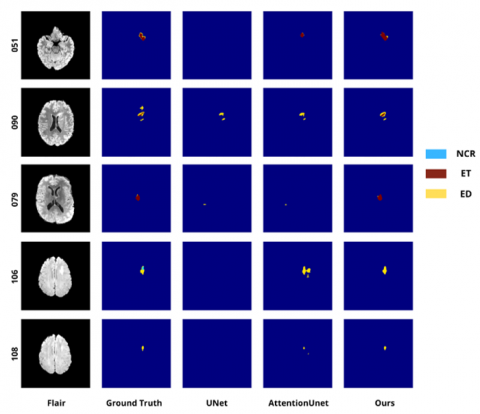

Figure 9. Segmentation results on the brain tumor segmentation (BraTS) dataset for tumors of small sizes

Table 5 shows that small-tumor segmentation remains a major challenge for baseline models, as these lesions occupy only a very limited area and often present ambiguous boundaries. In many cases, U-Net fails to generate meaningful predictions, as evidenced by Dice scores of 0 for the edema (ED) and enhancing tumor (ET) regions. Although Attention U-Net provides a slight improvement, its performance remains unstable and it still tends to miss tumor regions that are very small or weakly visible. In this table, “–” indicates that the corresponding class is not present in the ground-truth (GT) annotation; therefore, the metric is not applicable for that case.

Table 5. Dice score comparison (%) for small tumors corresponding to Figure 9

In contrast, the proposed model achieves better performance and shows higher sensitivity in detecting small lesions, especially in the ET region, which is important for assessing tumor malignancy. In addition, the clear improvement in the ED region suggests that our method can better capture diffuse tumor patterns even when the lesion appears at a very small scale. These results confirm the effectiveness and reliability of the proposed model in difficult cases, where traditional approaches often fail or provide incomplete predictions.